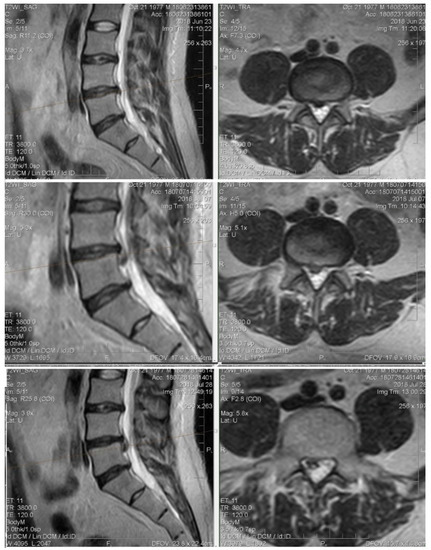

4.2. Clinical Case 1 (Dexamethasone Group)

Patient M., 64 years old, complains of intense back pain with spreading to the left leg, tingling in the foot. Clinically: VAS 8. The straight leg test is left-angled to 30°. Achilles reflex is absent left-sided, hypoesthesia in the dermatome S1.

Initial MRI: The extrusion of the intervertebral disk L5–S1 up to 8 mm with stenosis of the foraminal channel is left-sided and compressed by the corresponding structures. With the treatment of dexamethasone, already on day 15 (the first control point), the VAS was 1–2 points, the volume of movements in full. However, neuroimaging for 15 and 30 days does not indicate changes in the intensity of closure plates (type Modic II) or the size of the hernia (Figure 6).

Figure 6. MRI of the lumbar spine images show a large extruded disc fragment at the L5-S1 level. Neuroimaging for 15 and 30 days does not indicate changes of the size of extrusion.